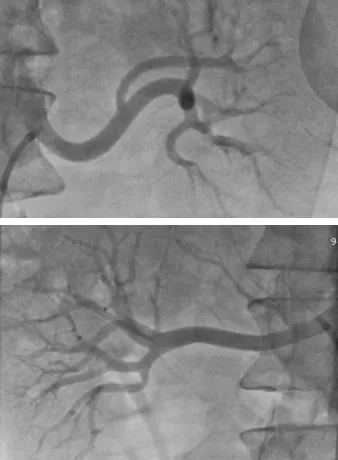

▲肾动脉造影提示双侧肾动脉迂曲